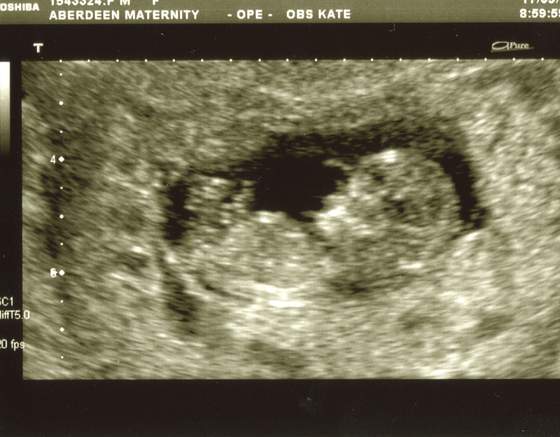

O ja rozumiem ze wszystko dobrze :-)a to nasza KRUSZYNKA![]()

wszystko jest w najlepszym porzadku dzidzia rosnie ma 5 cm... serduszko bije jak szalone - dla mamusi![]()